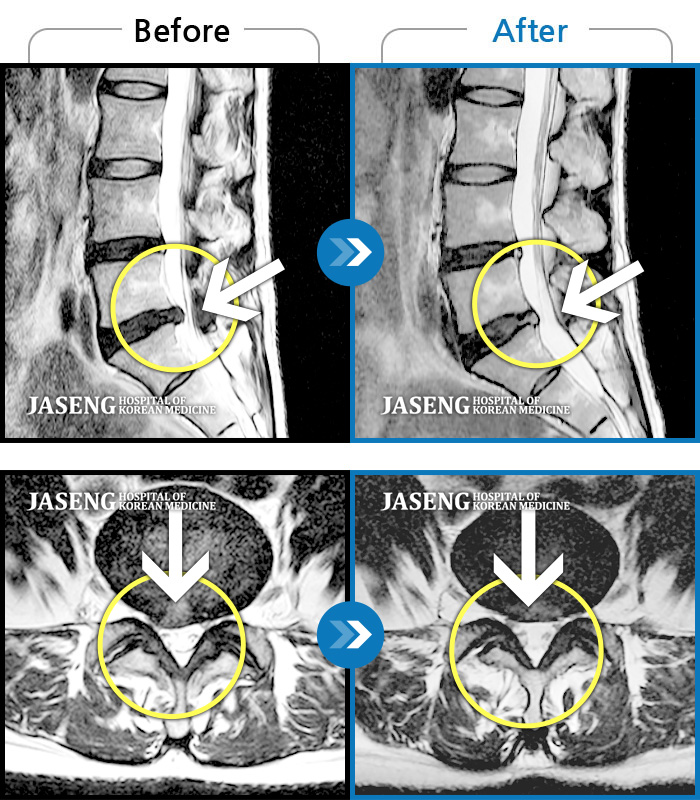

Before

After

환자에게 사전 동의를 받아 동일 조건에서 촬영되었습니다.

개인에 따라 치료 후 부작용이 발생할 수 있으니 의료진과 상담 후 치료를 진행하시기 바랍니다.

앉지도 서지도 못하는 극심한 요통, 하지방사통으로 응급실 내원

좌측 허벅지 종아리가 전기오듯 당기고 발바닥 저림이 있었다.